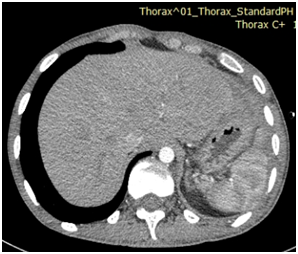

Then the patient was shifted for a computed tomography (CT) of thorax and abdomen (Figure1) which showed herniation in the left lower lung zone of the bowel loops through the disrupted left hemi diaphragm, with multiple air fluid levels. The herniated abdominal contents are positioned against the posterior wall of the thorax (dependent viscera sign).The collar at the base of the herniated bowel is more difficult to detect on the axial CT image than on reformatted images in other planes. Default of enhancement of the wall signs the ischemia. Diagnosis of complicated diaphragmatic hernia was made. Emergency surgery was decided with reduction of the hernia, Segmental colic resection. The patient was extubated and hospitalized. On follow-up, vital signs were stable and radiological examination was normal (Figure 2). The patient was discharged on the third day postoperatively.

Figure 2 Postoperative CT scan showing expansion of the previously collapsed left lung.